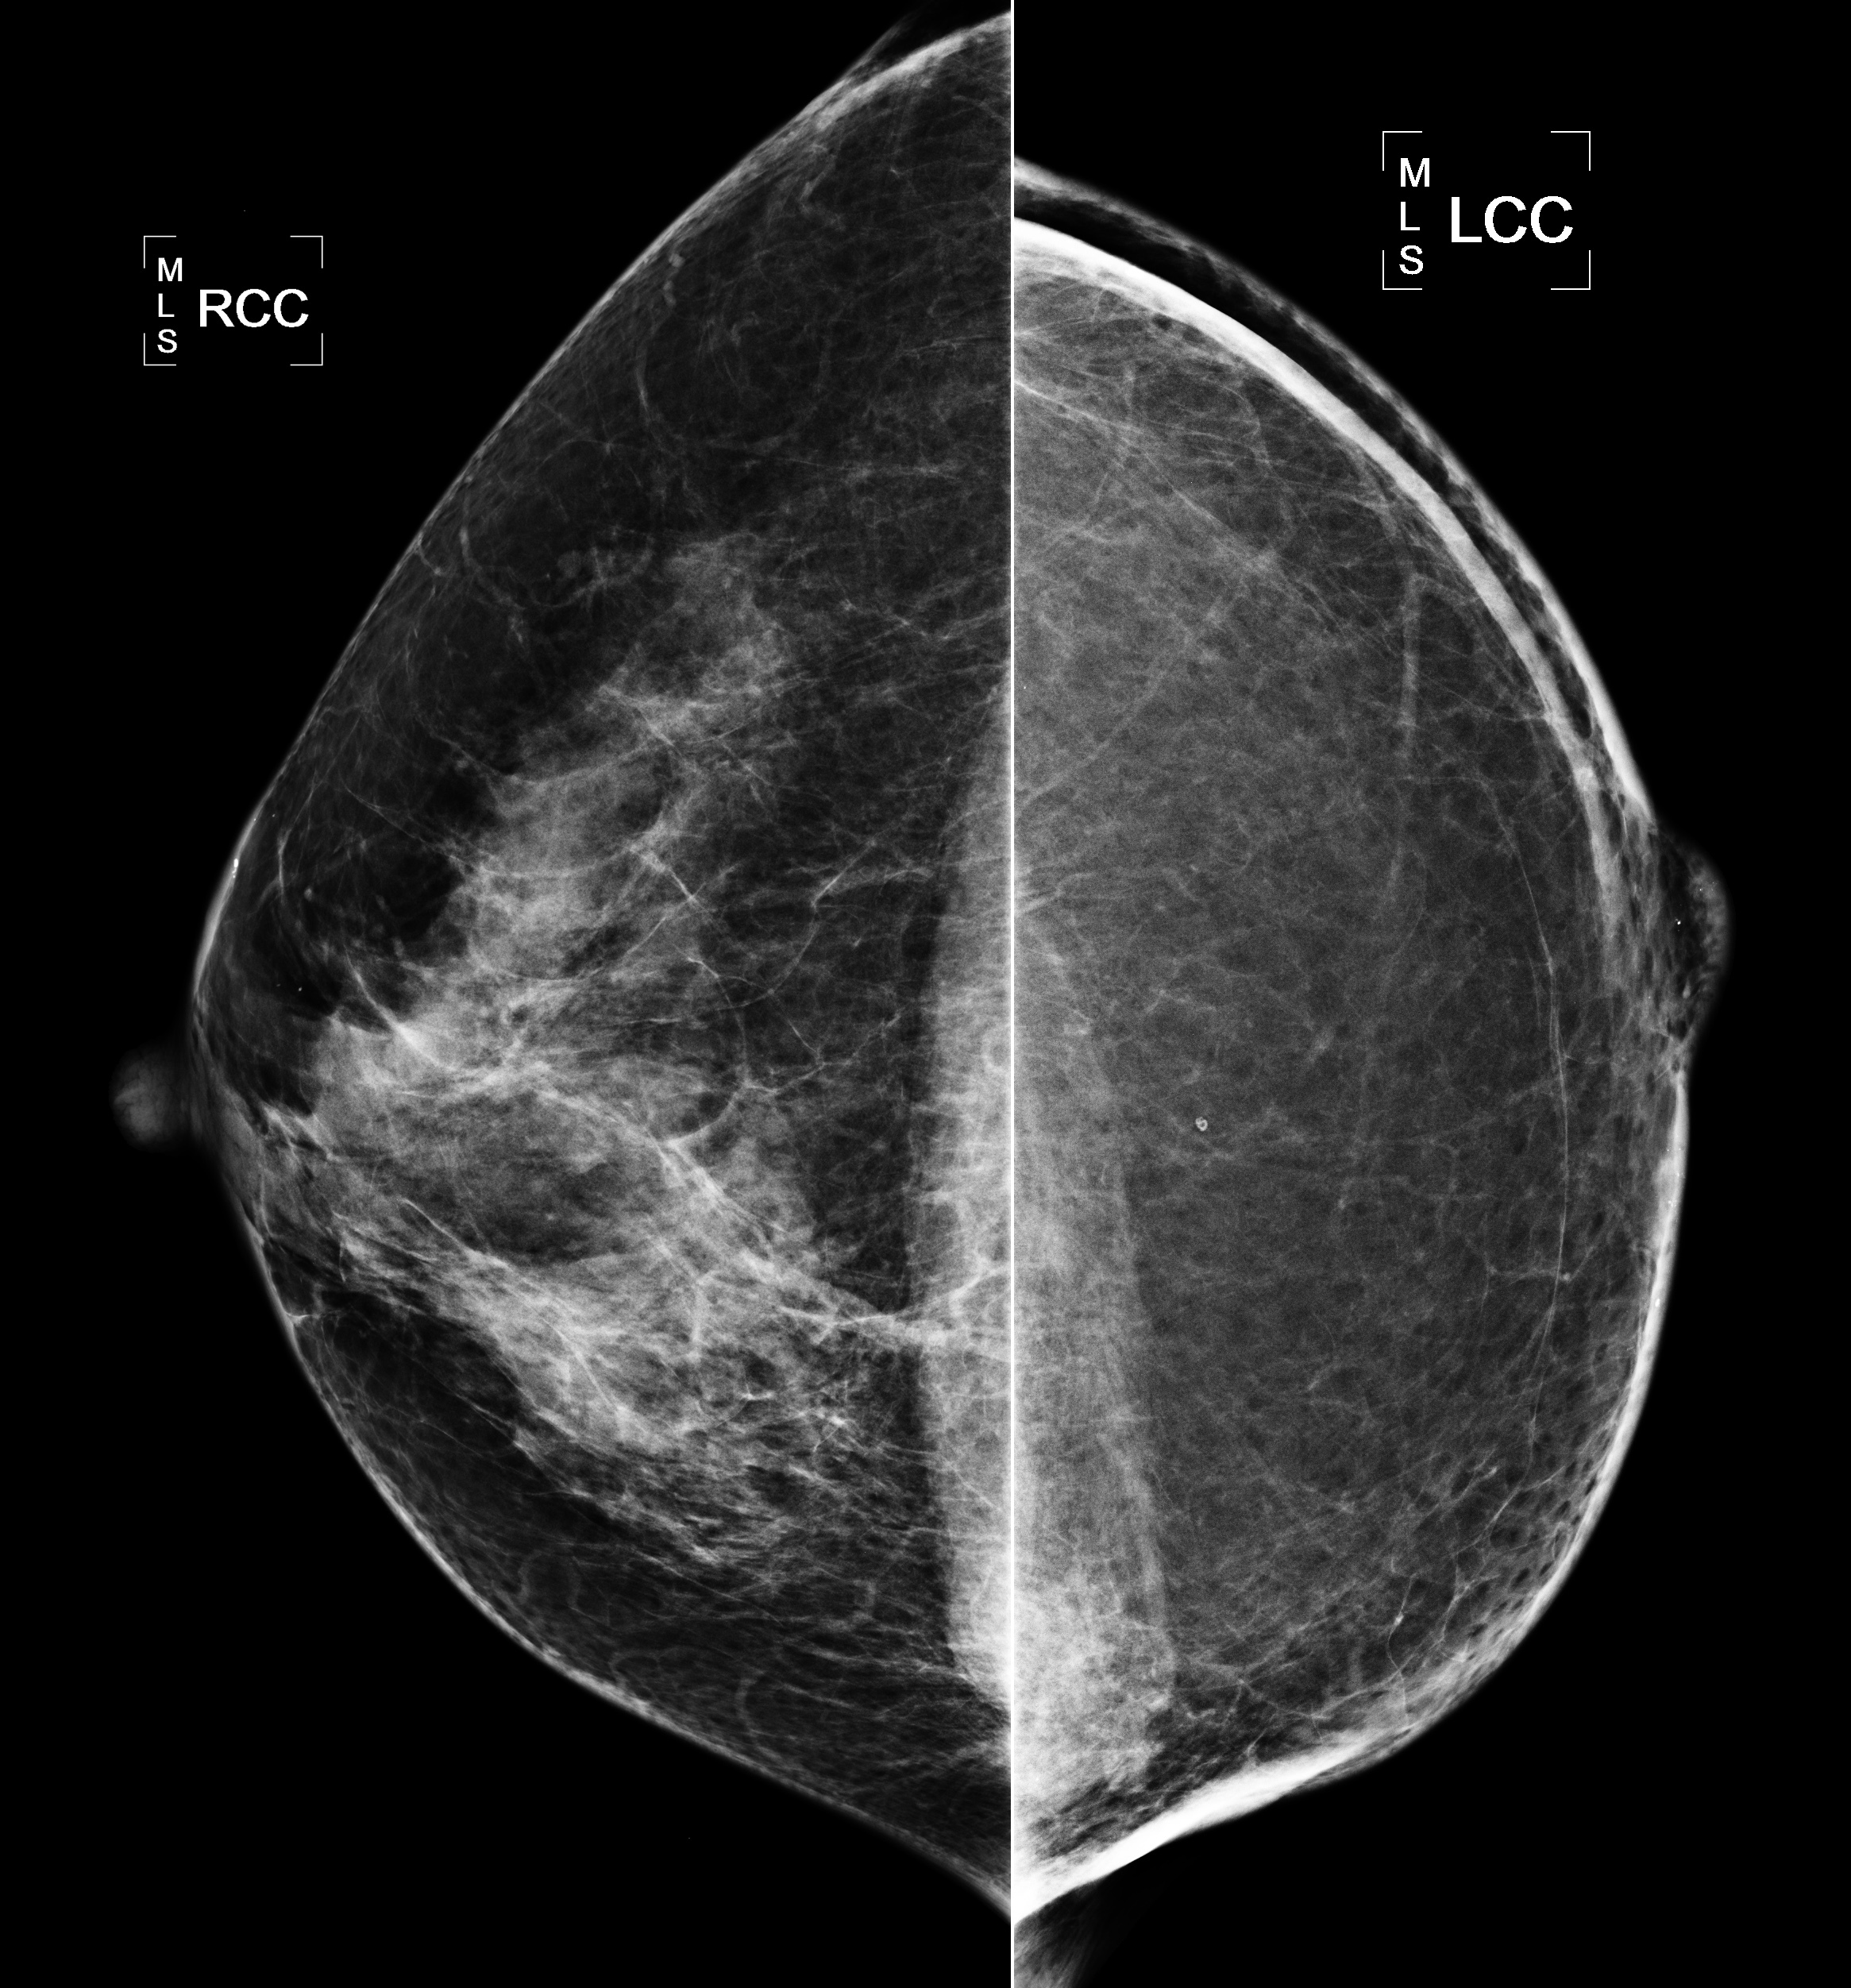

◂Breast Anatomy